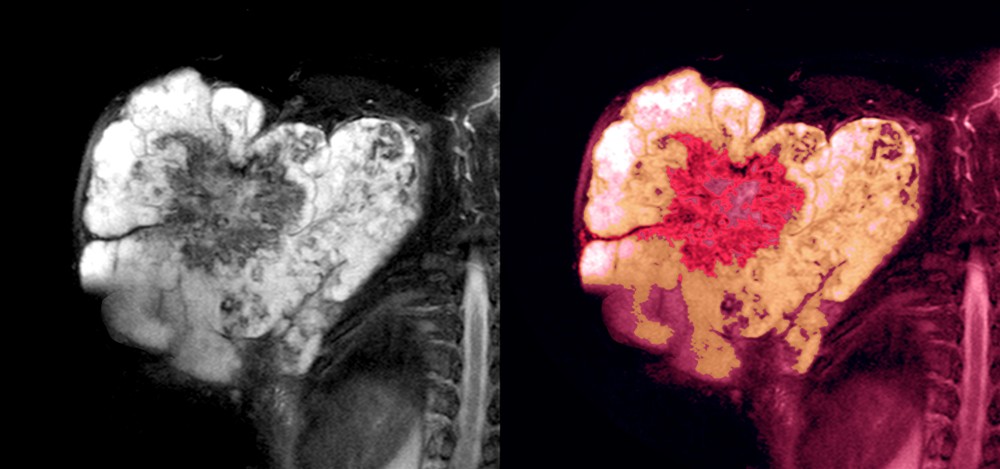

סרקומה הינה שאת ממאירה ממקור הרקמות המהוות את מערכת השלד והתנועה, העצבים ההיקפיים, כלי הדם, השומן או דפנות האיברים השונים. שכיחות הסרקומות בכלל היא 1% מכלל השאתות הממאירות.

סר"ר יכולות להתפתח למעשה בכל איבר בגוף: גפיים, איברים פנימיים (קיבה, מעי, כליה, ראה, מוח, שד, מערכת השתן והמין, ועוד), דופן הבטן, החזה או הגב. קיימים סוגים רבים של סר"ר בהתאם לרקמה הרכה ממנה נוצר הגידול.

הממצא הקליני השכיח ביותר הוא הופעה של גוש מקומי ההולך וגדל תוך מספר חודשים. כאשר הסרקומה מופיעה בגפה  ניתן לחוש בגוש נוקשה נייד למחצה, ההולך וגדל,  ומלווה תפיחות הרקמות הרכות סביבו, ולעיתים חום ואודם מקומיים. כאשר מתפתחת הסרקומה באיבר פנימי ההסתמנות הקלינית קשורה בתפקוד לקוי של האיבר הנגוע. פרק הזמן הממוצע החולף בין תחילת ההסתמנות בסרקומה של גפה לבין קביעת האבחנה הוא 3-6 חודשים. בכל מקרה בו נחשד קיומה של סר"ר יש לפנות לצוות-מומחה לטיפול בסרקומה, הפועל ביחידה משולבת של אורטופדיה-אונקולוגית.